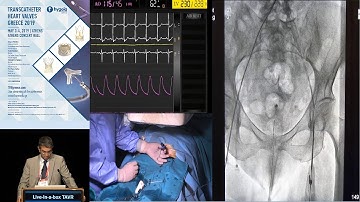

Discussion | TAVI Session IV – Avoiding Pitfalls